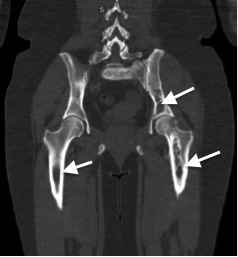

- На мультиспиральной КТ (МСКТ)левого тазобедренного и коленного суставов визуализированы зоны кистовидных перестроек и участков остеосклероза, преимущественно в области лобковой и седалищной костей, а также проксимальной трети левой бедренной кости; искривлена ось левой бедренной кости по типу «хоккейной клюшки». В структуре проксимальной и средней трети бедренной кости — две полости, содержимое которых представлено солидным содержимым, вероятно, фиброзной тканью. На уровне дистального отдела бедренной кости и проксимального отдела большеберцовой кости — множественные участки кистовидной перестройки, фрагментации костной ткани, местами с нарушением целостности и истончением кортикального слоя. КТ-картина соответствовала ФД (полиоссальная форма) костей таза слева, левой бедренной и большеберцовой костей (рис. 5–7).

Рис. 5. Пациентка М. Очаги фиброзной дисплазии в крыле подвздошной кости и в межвертельной области бедренной кости.

Рис. 6. Пациентка М. МСКТ таза, 3D-реконструкция. Полиоссальная форма фиброзной дисплазии. Зоны кистовидных перестроек (стрелки) в костях таза и левой бедренной кости, преимущественно расположенных в области подвздошной, лобковой костей, крестца слева, а также в проксимальной трети левой бедренной кости.

Рис. 7. Пациентка М. МСКТ левого тазобедренного сустава, корональная плоскость. Полиоссальная форма фиброзной дисплазии. Ось левой бедренной кости искривлена по типу «хоккейной клюшки». Шеечно-диафизарный угол 97° (норма 125–135°). Шейка деформирована, утолщена. В структуре проксимальной и средней трети бедренной кости определяются две полости (длинные стрелки). Содержимое полостей представлено солидным содержимым плотностью 65 ед. Н (фиброзная ткань). Кортикальный слой на границе проксимальной и средней трети неравномерно утолщен с периостальными костными наслоениями (консолидированный перелом?) (короткая стрелка).